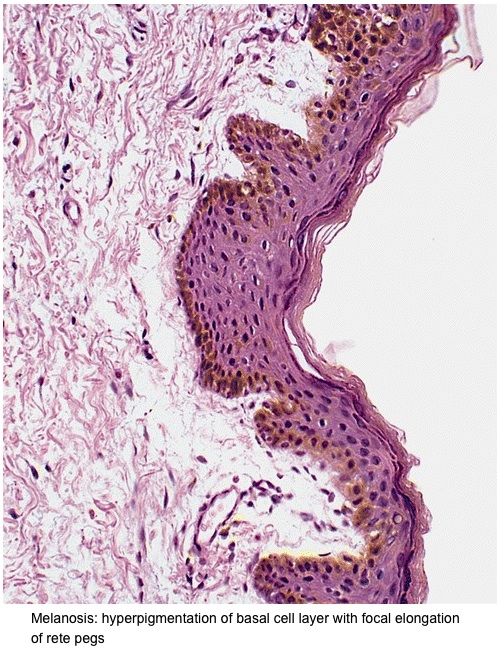

Penile melanosis, also referred to as penile lentigines or penile freckling, is characterized by the presence of dark spots or patches on the skin of the penis. These spots can vary in size and number and can appear anywhere on the penis, from the head (glans) to the shaft. The condition arises from an accumulation of melanocytes, the cells responsible for producing melanin, the pigment that gives skin its color. These melanocytes clump together, leading to the formation of dark brown or black dots.

While generally harmless, it's understandable why individuals might seek more information. Although genital melanosis is considered benign, some research has indicated a potential link between genital melanosis and malignant melanoma. One study reported that melanosis was the most common pigmented lesion in the genital region, and that the glans penis was the most frequent location for pigmented lesions in males [4]. Therefore, understanding the subtle differences and knowing when to seek professional medical advice is critical.

Treatment options for penile melanosis include laser therapy or surgical removal. Dermoscopic findings revealed a fibrillar pattern, indicating a potential diagnosis of penile melanosis. Histopathological analysis of a skin biopsy specimen confirmed keratinocyte hyperpigmentation and ruled out any melanocytic abnormalities or proliferation, supporting the diagnosis of penile melanosis.

Indeed, one of the major mimickers of mucosal melanoma, and thus of penile melanomas, is melanosis. Clinically, despite its benign behavior, melanosis can, at times, share features with malignant melanoma: asymmetry, irregular borders, multifocality, variegated pigmentary patterns and large size. Lumps under the skin in the groin area. If the cancer spreads from the penis, it most often travels first to lymph nodes in the groin. This can make those lymph nodes swell.

Penile melanosis is an accumulation of melanocytes in the skin of the penis. These cells clump together in a single space and cause melanosis spots, which are dark brown or black dots. It is unknown why melanocytes accumulate this way, and the exact causes of penile melanosis are unknown.